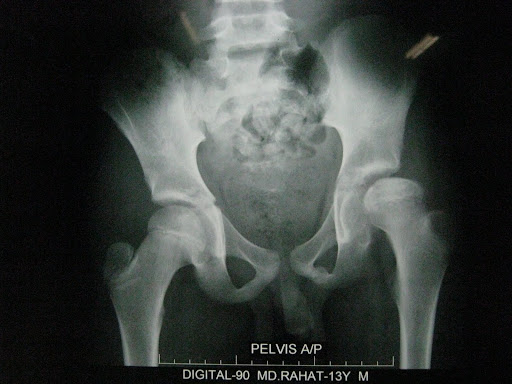

Perthe's disease of left femoral head